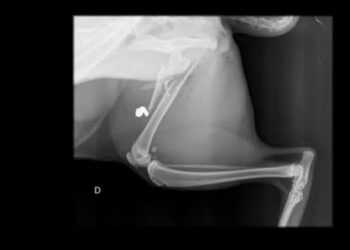

DISTRITO FEDERAL | Um gato foi atingido na perna por uma bala perdida na última sexta-feira (17) no condomínio Solar ...